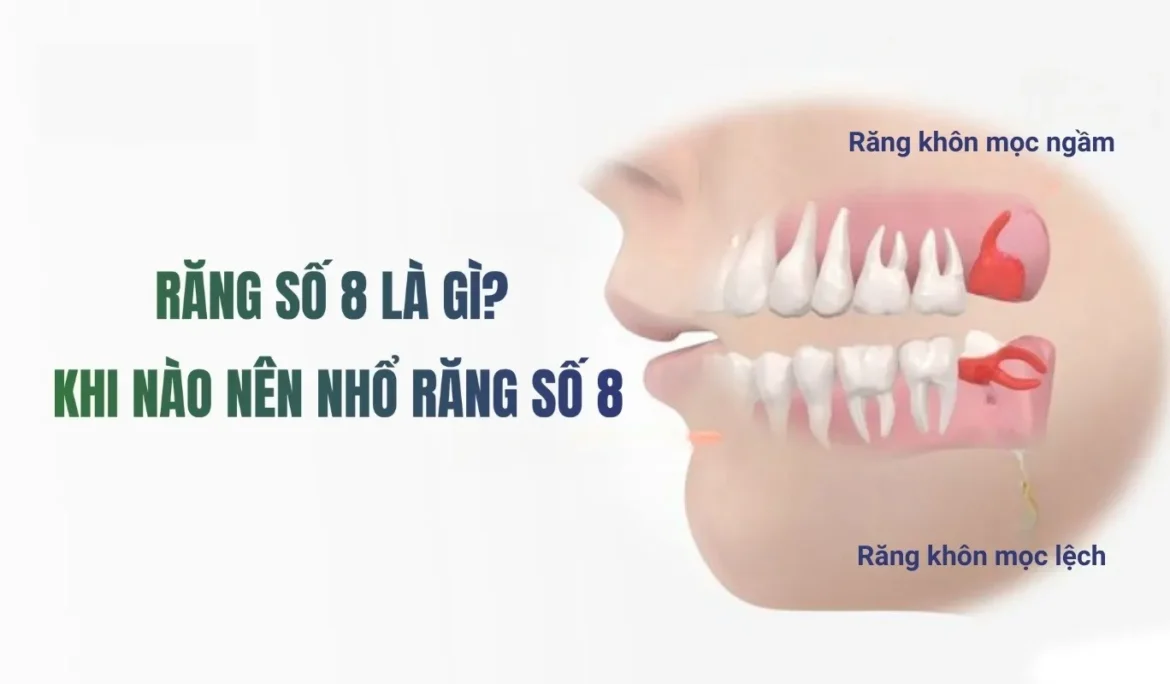

Răng Số 8 Là Gì Và Tại Sao Dễ Mọc Ngầm

Vì sao răng số 8 thường bị mọc ngầm (cung hàm không đủ chỗ, xương đã cứng…)

- Cung hàm không đủ chỗ: Đây là nguyên nhân phổ biến nhất. Khi răng số 8 bắt đầu mọc, toàn bộ các răng khác trên cung hàm đã ổn định vị trí. Nếu xương hàm của bạn có kích thước nhỏ hoặc các răng khác quá lớn, không còn đủ khoảng trống, răng khôn buộc phải tìm đường mọc theo hướng bất thường, dẫn đến mọc nghiêng, mọc lệch hoặc mọc kẹt, mọc ngầm hoàn toàn dưới nướu và xương hàm.

- Sự cản trở từ răng số 7: Răng 8 mọc ngầm thường gặp sự cản trở từ chân hoặc thân răng số 7 ở phía trước, khiến nó không thể trồi lên đúng vị trí thẳng đứng.